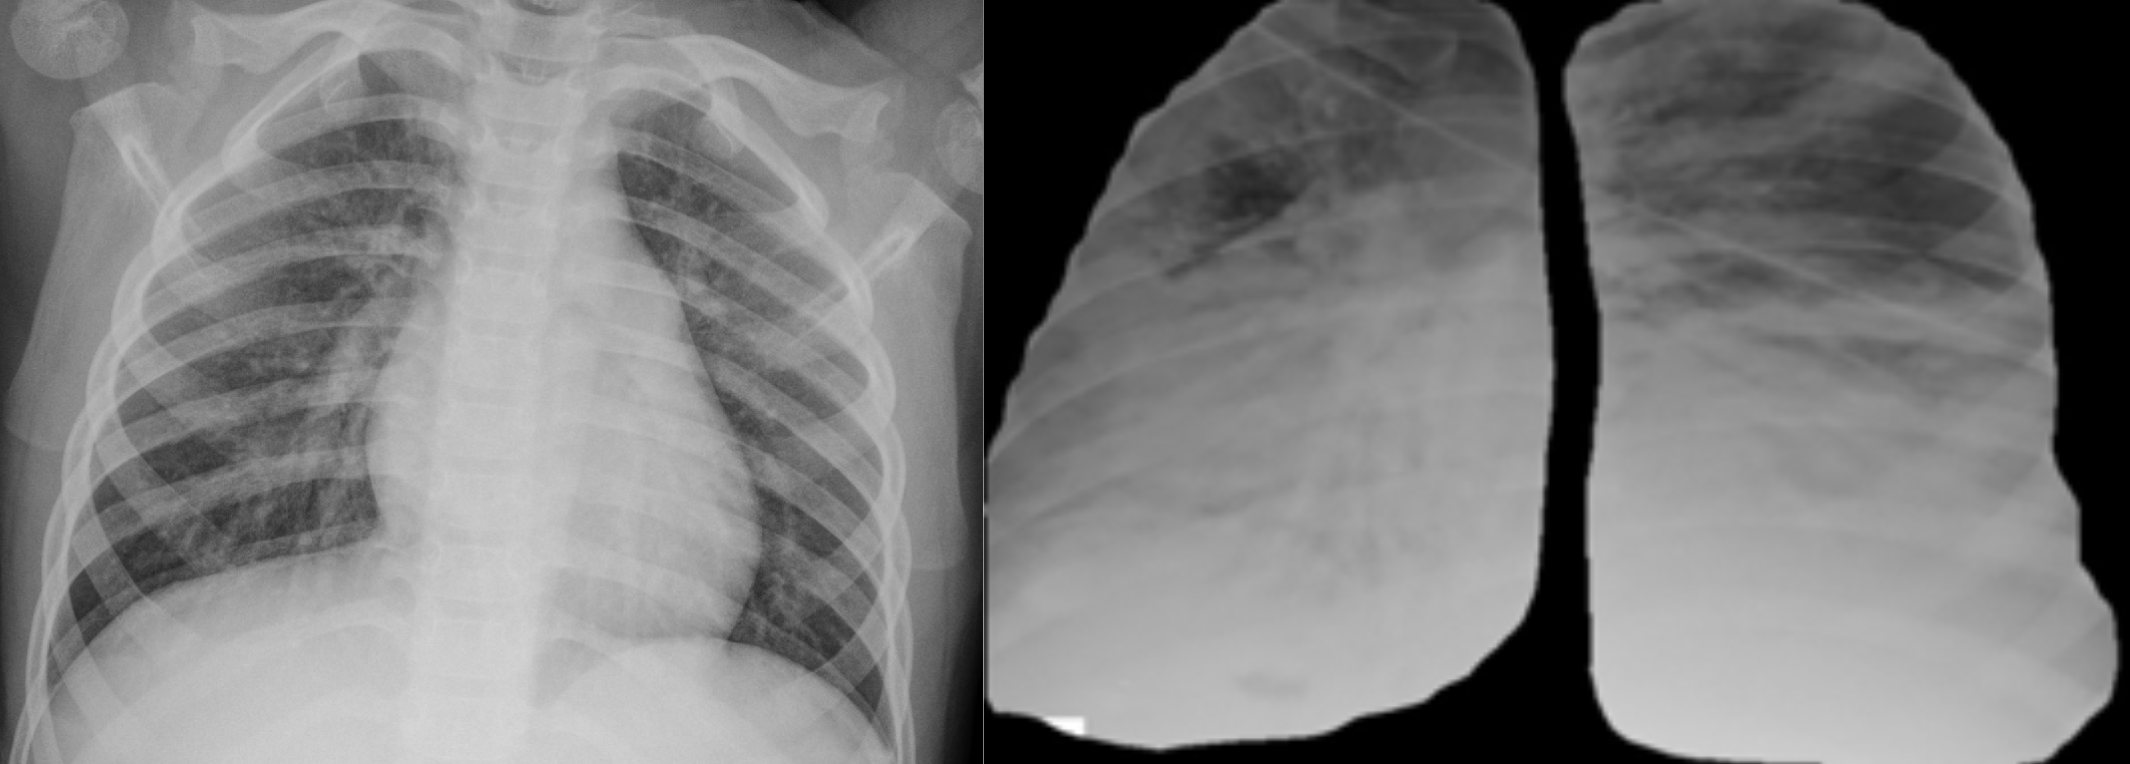

Diagnostics Free FullText SegmentationBased Classification Deep Covid Chest X Ray Dataset Github  There are 517 cases of covid. We also introduce covidx, an open access benchmark dataset that we generated comprising of 13,975. Covidx dataset | papers with code. Covid Chest X Ray Dataset Github.